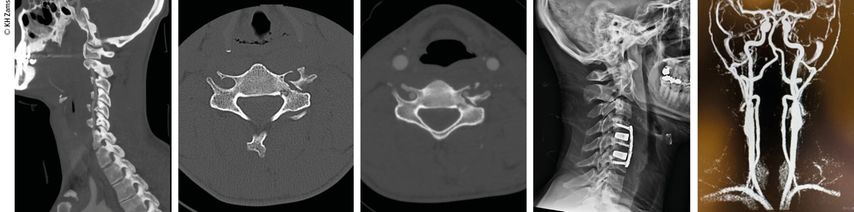

Abb. 2: Fallbeispiel: Mann, 57a, Z.n. Fahrradsturz, stabile Fraktur des Proc. artic. C2 r. mit Dissektion der A. vertebralis r. mit asymptomatischem Substanzdefekt im hinteren Stromgebiet (cMRT), Heparintherapie initial, anschließend APT